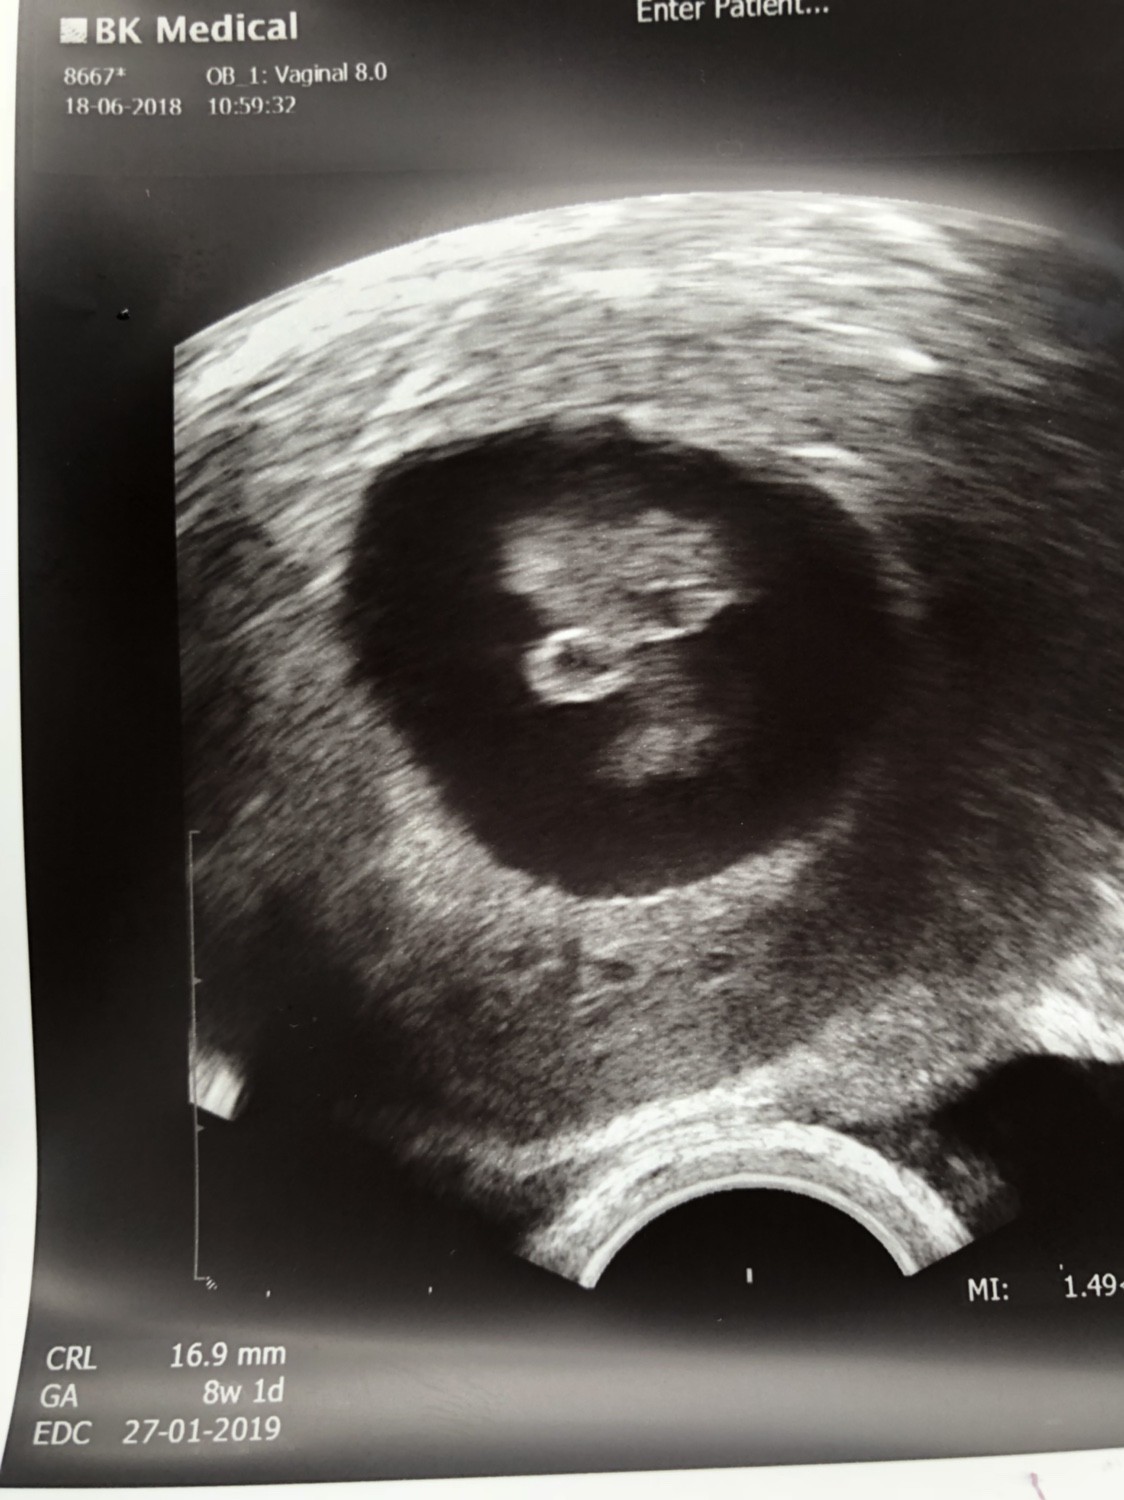

ja już po wizycie synuś waży 560g , niestety łożysko mam za nisko i czeka mnie leżenie narazie na kolejne trzy tygodnie, być może jeszcze się podniesie do góry